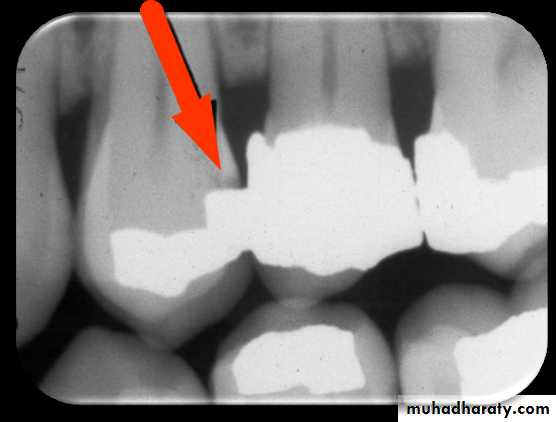

Occlusal Caries

A thorough clinically examination is the method of choices for detection of occlusal caries

Because of superimposition of dense buccal and lingual enamel cups early occlusal caries is difficult to see on a dental radiograph

Occlusal caries classified into

Incipient occlusal caries cannot be seen on a dental radiograph and must be detected clinically with dental probeModerate occlusal caries extends into dentin and appears as a very thin radiolucent line located under the enamel of the occlusal surface

Severe occlusal caries extends into dentin and appears a as large radiolucency under the enamel of occlusal surface of the tooth clinically appears as a cavitations into a tooth.